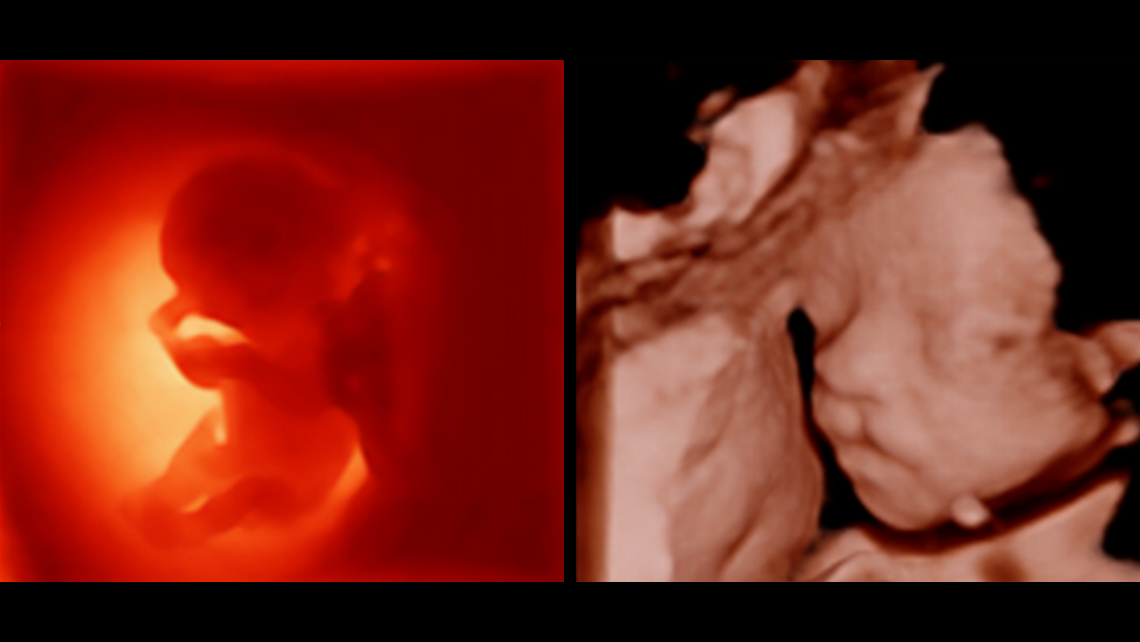

Klinik G?rĂŒntĂŒler